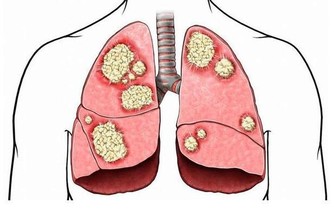

半夜3點到5點是器官正常的排毒時間,如果你常在這時間醒來,有可能是肺部氣血不足、流通不順暢,身體會開啟自愈模式,提醒你醒來,使得肺部器官不至於因氣血不足虛勞受到損害。